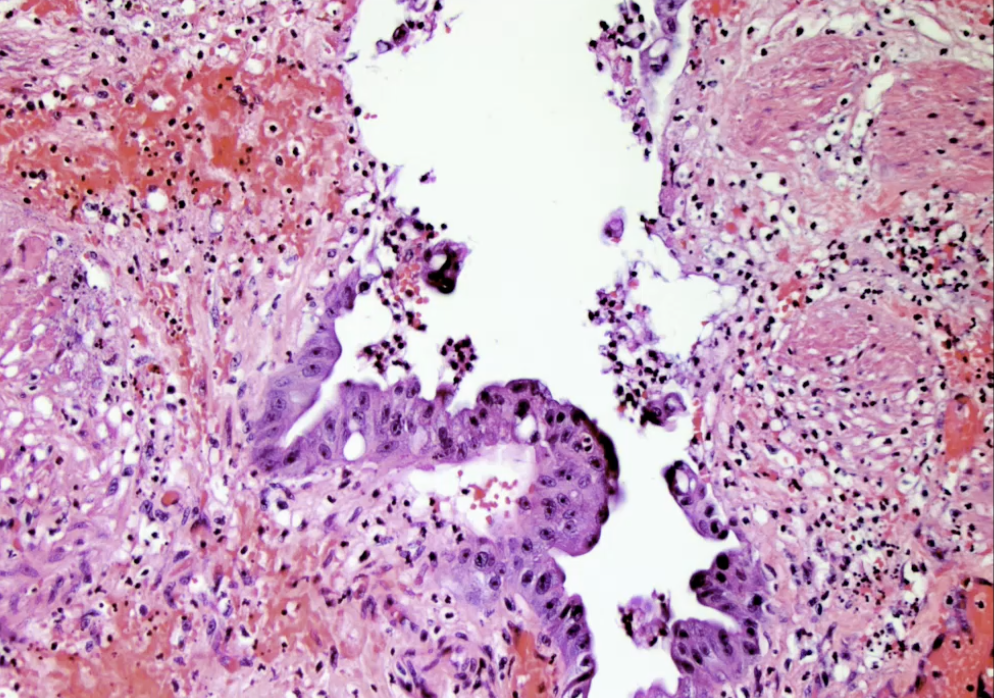

Adenocarcinoma of the Gallbladder